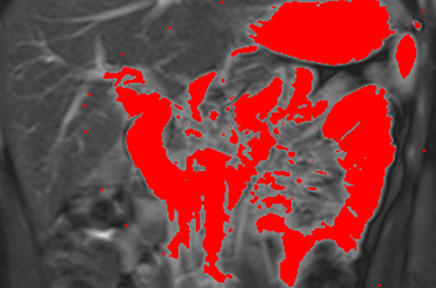

Functional imaging for individualised cancer treatment (Professor Ingfrid Haldorsen).

The research group aims to:

- Explore functional imaging findings i.e. potential imaging biomarkers that predict advanced tumor stage, lymph node metastases and reduced survival in patients with uterine cancers.

- Validate and compare these imaging biomarkers with established histomorphological and molecular biomarkers in uterine cancers.

- Implement these imaging biomarkers in the preoperative risk stratification to enable better tailored and individualized treatment of uterine cancers.

- Explore functional imaging findings in an orthotopic animal model of primary and metastatic lesions of uterine cancers.

- Explore imaging characteristics as tools to detect early drug response in orthotopic tumour grafts.